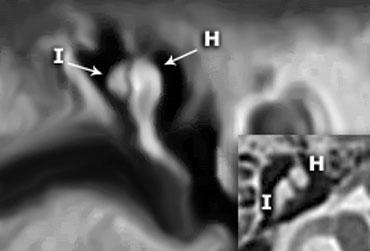

Tái tạo coronal cho thấy rõ ràng xương đe (I) nằm ở phía sau-ngoài so với đầu xương búa (H). Trên hình axial, mỏm ngắn của xương đe được thấy chỉ về phía sau-ngoài.

Trong nhiều hình minh họa, bạn sẽ thấy xương đe kết nối vào phía trong của xương búa, nhưng điều này không chính xác.

Trên hình tái tạo coronal bên trái, có thể thấy rõ ràng rằng xương đe nằm ở phía sau-ngoài so với đầu xương búa.

Ngành dài của xương đe sau đó chạy xuống dưới-vào trong đến xương bàn đạp.